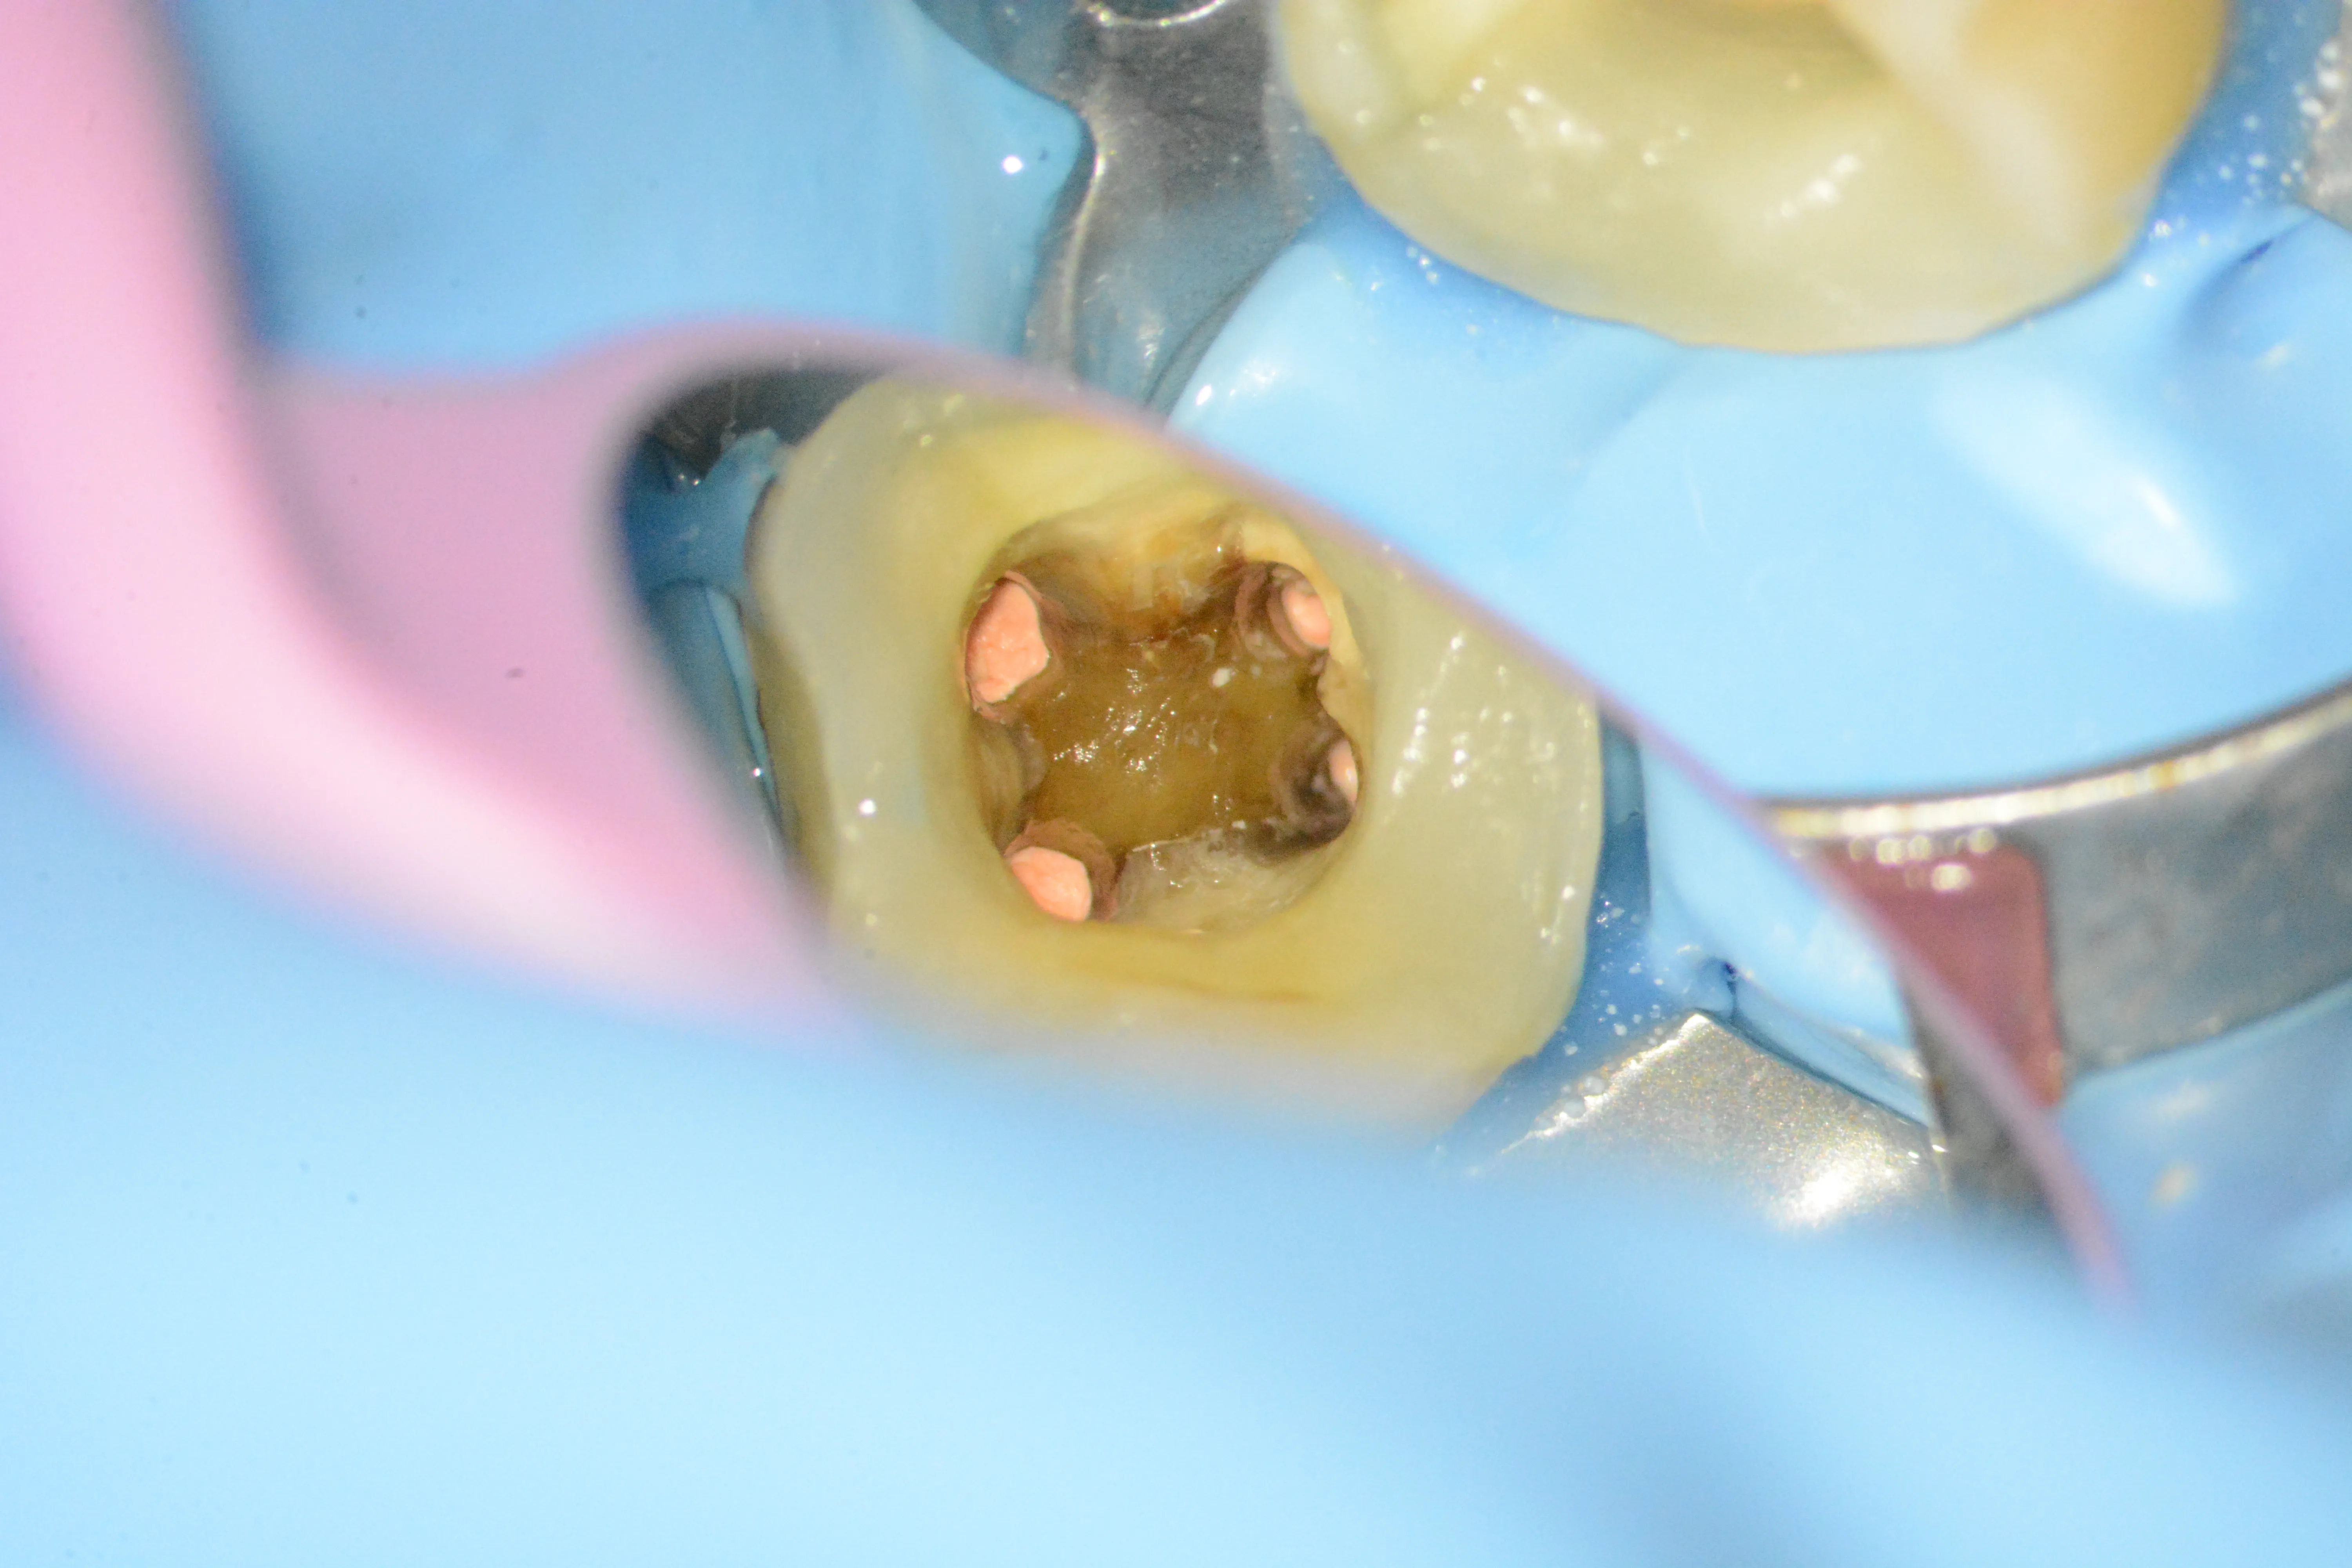

9 – Aspectul instrumentului fracturat expus